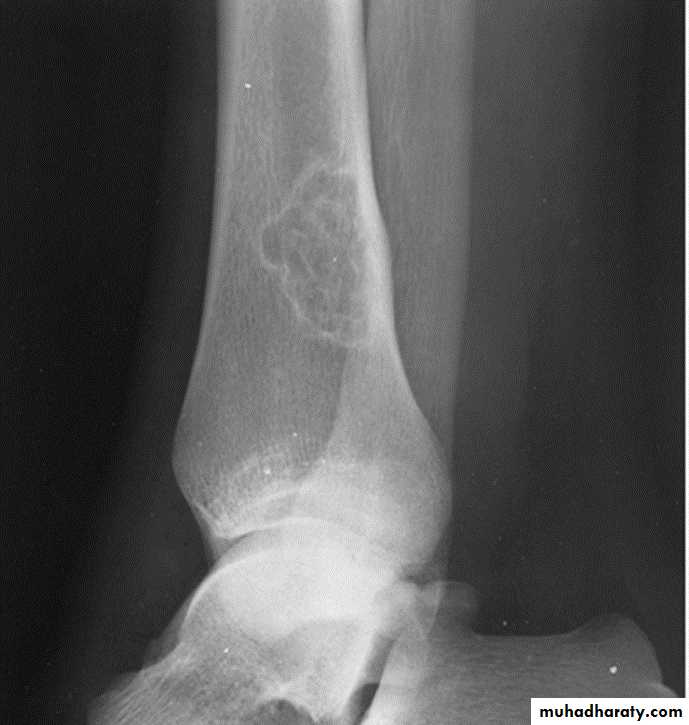

lytic, expansile lesion, Sub articular in location give the soap bubble appearance

*Soap bubble appearance (giant cell tumor )

Q….lytic, expansile lesion, Sub articular in location, Not clearly defined margin with thinning of the cortex ???

Giant cell tumor